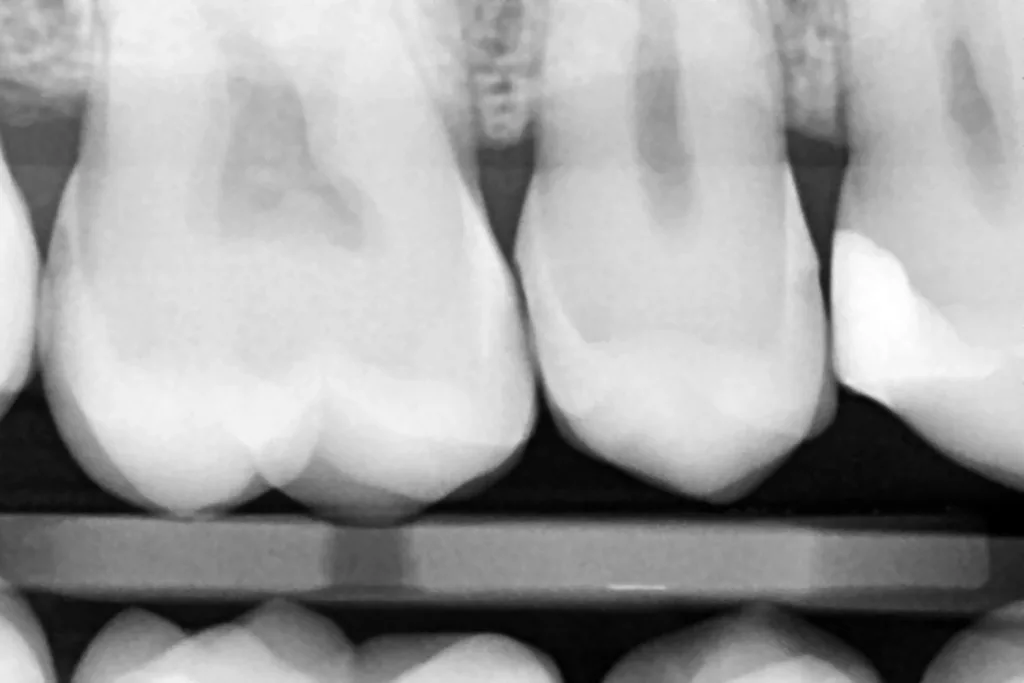

Die Abbildung 10 zeigt das Behandlungsergebnis unmittelbar nach Ausarbeitung und Politur (Diacomp Plus Twist, EVE), die Abbildung 11 bei einer weiteren Kontrolle nach sechs Monaten. In diesem Kontrolltermin wurden dann im routinemäßigen, zwei- bis dreijährigen Intervall Bissflügelröntgenaufnahmen zur Kariesdiagnostik angefertigt. Auf der Röntgenaufnahme zeigt sich die neue Visalys-Bulk-Flow-Restauration als randdicht, anatomisch korrekt geformt und ausreichend röntgenopak (Abb. 12). Die Schmelzläsion mesial an den Zähnen 15 und 16 erschien nicht therapiebedürftig, da die Oberfläche intakt war, wohl aber die versteckte Dentinläsion distal an dem Zahn 15. Der Defekt wurde in einem weiteren Termin identisch mit denselben Materialkombinationen und identischem Polymerisationsprotokoll versorgt (Abb. 13 bis 15).